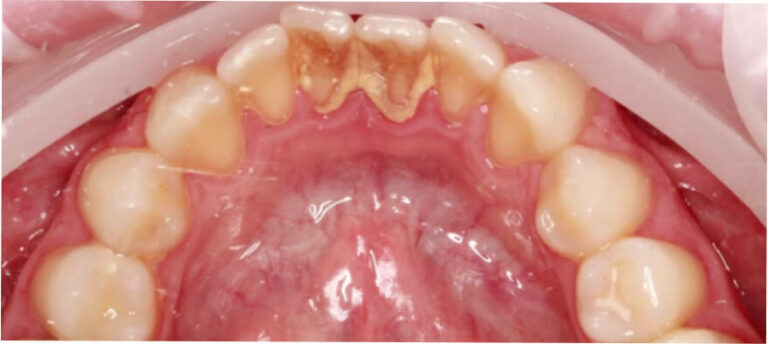

Po

Higienizacja